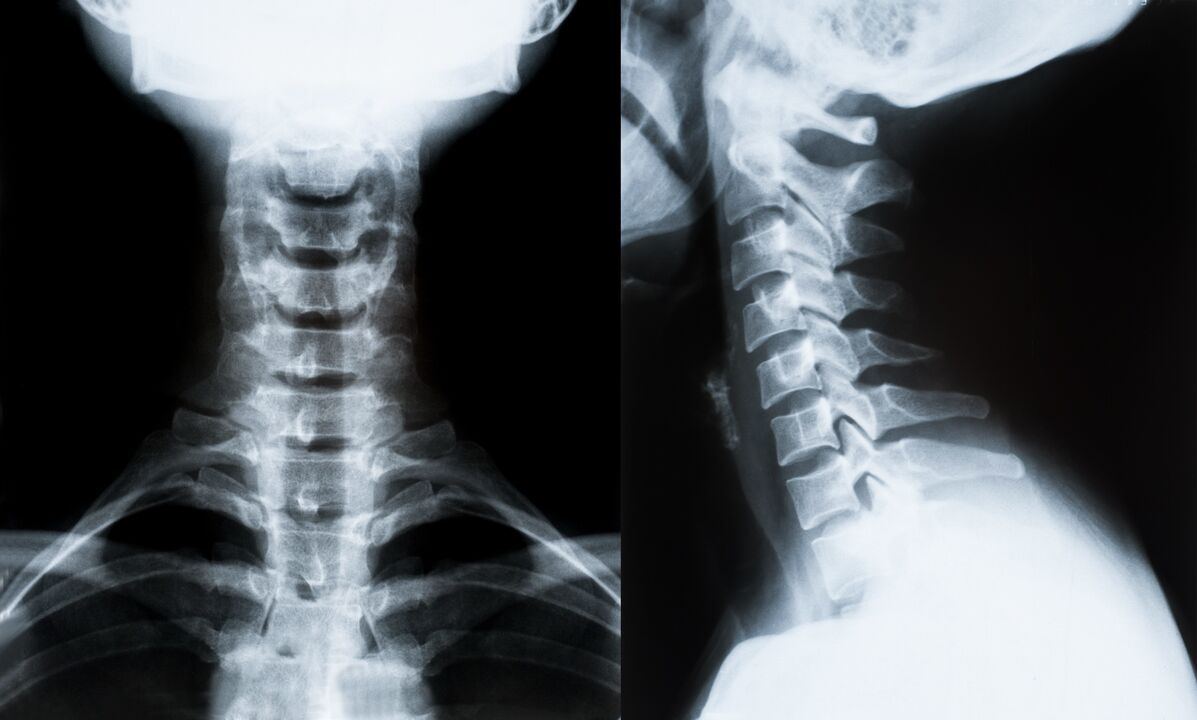

Les principales méthodes de diagnostic et de détermination du traitement de l'ostéochondrose de la colonne cervicale :

- Roentgen. La méthode de diagnostic la moins efficace, mais traditionnelle.

- L'imagerie par résonance magnétique est la méthode de diagnostic la plus efficace. Avec ce type d’examen du patient, toutes les structures nécessaires sont visibles.

- Si les changements doivent être mesurés, la tomodensitométrie est utilisée. Détermine la présence de hernies et d'autres choses.

- La dernière méthode est l’examen écho-Doppler. Cette méthode de recherche détermine la vitesse du flux sanguin dans les artères.